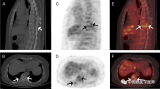

傅璠:《68Ga-FAPI PET/MR在急性心梗后早期心肌成纤维细胞激活及心功能预测的研究》

以往FAPI PET应用主要集中于肿瘤学,在良性纤维化疾病的应用论文报道较少。这篇文献点出了FAPI PET显像在心脏疾病中的应用价值之一,其不仅比较了PET与MR信号之间相关性及差异性外,最重要的一点是提示FAPI与心梗预后的显著相关,具有良好的应用前景。 2022-08-18 PET/CTPET/MRI